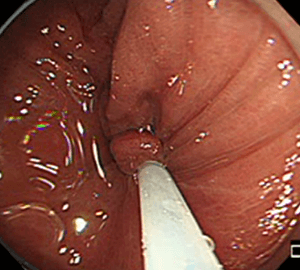

6:切除後に洗浄・観察して、病変の遺残がないことを確認します。6:切除後に洗浄・観察して、病変の遺残がないことを確認します。

少量の出血であれば経過を見ることができます。コールドスネアポリペクトミー後の出血はほとんどが少量ですぐに止まりますので、特段の処置を必要としません。またEMR後の一部などでは止血を要することがありますが、その場合でもほとんどで内視鏡的に止血を行うことが可能です。